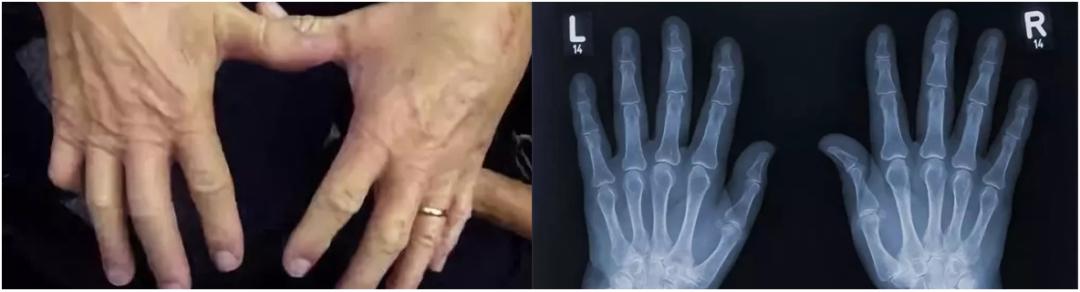

从 1948 年到 1998 年 ,已是医学博士的唐纳德把左手掰了至少 36500 次。

而 50 年后,他两只手的状态,无论是肉眼所见还是 X 光影像,并没有任何差别,都很健康。

图片来源:网络

掰手指 ≠ 关节炎,虽然,把这个结论拿来反驳妈妈早已来不及了。

这项研究一共包含了 135 个实验组和 80 个对照组,通过比较参与者五年间的手指 X 光来进行判断。

结果再一次验证了老爷子的较真:掰手指和关节炎没关系。